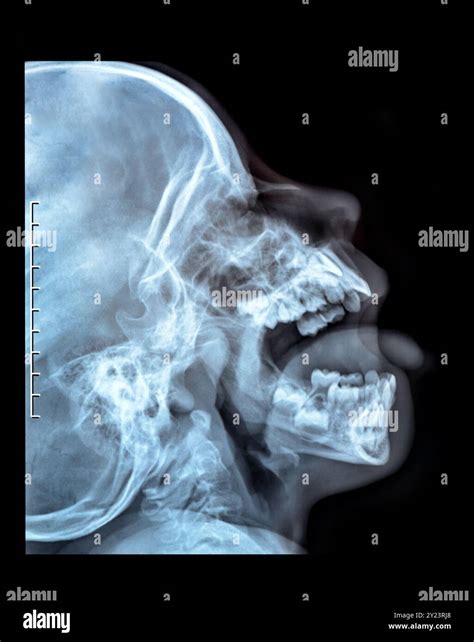

• X-Rays: X-rays are commonly used to visualize the bone and identify fractures.

• CT Scans: In more complex cases, a CT scan may be ordered to provide a detailed view of the jaw and surrounding structures.